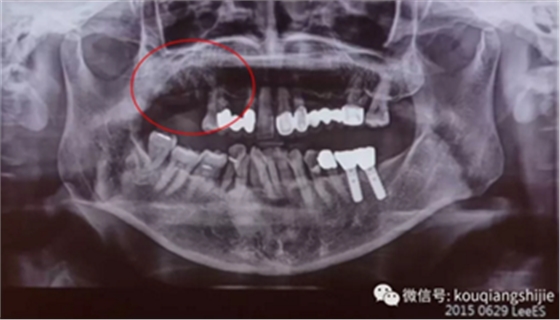

这个患者是在别的医院拔牙后1个月来到我们医院

我们从CT上可以看到#16,17的拔牙创破坏非常严重

但是因为是刚拔牙1个月,所以我觉得这个拔牙创应该可以愈合

我们再多等了3个月

3个月后我们发现缺损部位的黏膜愈合的非常不规则

翻瓣后发现也没有完全形成骨质。